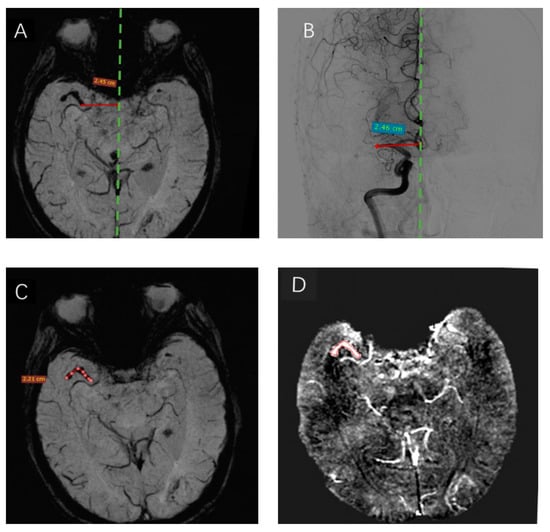

Primary SWI data with complete phase and magnitude images were processed, and the unwanted low signal regions outside the brain were removed using a Brain Extraction Tool (BET) in FMRIB Software Library (FSL) [15]. The background phase was reduced by a 96 × 96 homodyne high-pass filter, and QSM data were generated by a truncated k-space division with a regularization threshold of 0.1 [16]. Subsequently, the data were analyzed using signal processing in nuclear magnetic resonance (SPIN) software (SpinTech Inc, Miamisburg, OH, USA). The thrombus susceptibility of the region of interest (ROI) of thrombi in the maximum area plane was measured by two experienced radiologists who specialized in MRI. The detailed measurements are shown in Figure 3D.

Figure 3.

SWI and DSA demonstration of the thrombus. A thrombus was visible in the right MCA on SWI (mIP). The distance from the proximal end of the thrombus to the midline on SWI (A) was highly similar to that measured on DSA (B). The length of the thrombus measured on SWI was 2.21 cm (C). (D) The ROI is drawn in axial view at the central slice of the thrombus, with a mean susceptibility value of 212.1 ppb (In red contour).

2.5. Measurement of the Length of Thrombi and Analysis

The location of the SVS was used to denote the position of the thrombus in relation to the midline. The midline was defined as a line connecting the occipital part of the superior sagittal sinus with the point midway between the A2 segments of the anterior cerebral arteries, as observed on axial images. The maximum thrombus length was measured on SWI using a previously published method [17]. The diagnostic series of DSA images were analyzed for the presence and location of the occluding thrombus according to the criteria used for SWI. The detailed measurements are shown in Figure 3A–C. The measurements were completed by two radiologists unaware of SVS on SWI and the location of the occlusion on SWI and DSA.

A total of 15 patients consisting of 40% males, mean age ot 73.47 ± 10.7 (range 59–88) years, were included in the final analysis. The clinical characteristics of these patients are summarized in Table 1. Among these patients, 10 had an occlusion of the M1, 3 had M2, and 2 had both the M1 and M2 segments. All patients underwent thrombectomy with successful retrieval of their thrombi. The gold standard DSA showed vessel occlusion in all patients. The average distance of the proximal end of the thrombi to the midline was 24.67 ± 8.43 mm and 24.62 ± 8.44 mm as measured by SWI and DSA, respectively (Figure 3A,B), there was no difference in the detection of thrombus initiation between the two groups. Also, the SVS of SWI can directly measure the curve of thrombi length of 2.21 cm (Figure 3C), and the mean thrombus length of 15 cases was 16.57 ± 4.6 mm. The susceptibility of each region of interest (ROI) of the thrombus was measured manually and shown directly by the SPIN software (Figure 3D). The mean susceptibility values of RBC-dominant thrombi and fibrin-dominant thrombi were 209.88 ± 11.32 ppb and 155.70 ± 28.20 ppb, respectively. The mean thrombus susceptibility of RBC-dominant thrombi was significantly higher than that of fibrin-dominant thrombi (p = 0.037).